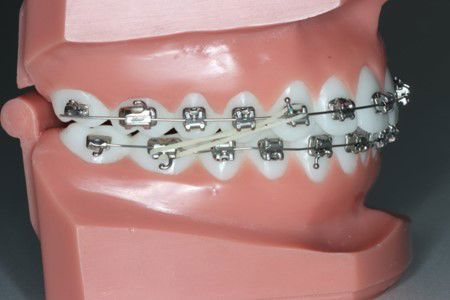

Bruges ofte sammen med fastsiddende apparatur til at gøre overbiddet mindre, kan også bruges til enkelttandskorrektioner, som f.eks. krydsbid.